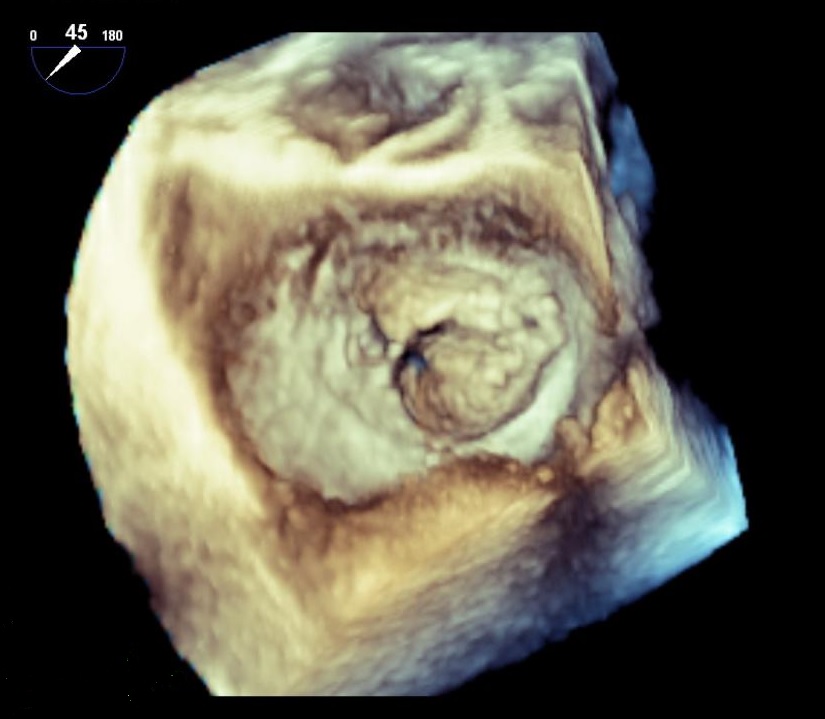

基本は二次元の断層図で評価しますが、必要に応じて三次元の立体像で評価し、手術前の検討などに役立てています。

心臓手術の前には3D経食道エコー図法も駆使し、手術精度向上に寄与しています。